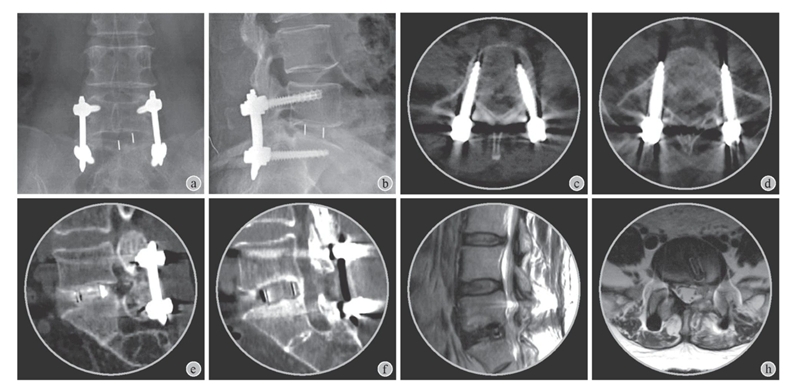

术后影像学评估:术后第2天复查X线片及CT显示椎弓根螺钉系统位置及长度合适,融合器位置位于L5~S1椎间隙中央(图6a~e)。术后第2天及术后3个月复查腰椎MRI显示椎管减压充分,神经根无受压征象(图6g~h)。术后6个月随访腰椎CT显示椎体间融合(图6f)。

图6 术后影像学评估

a~b:术后X线片显示椎弓根螺钉系统及椎间融合器位置及长度合适;c~d:术后轴位CT显示椎弓根螺钉位置正常;e:术后第2天CT显示椎间融合器位置及长度合适;f:术后6个月CT矢状位重建显示椎体间骨性融合;g:术后3个月矢状位T2加权MRI显示神经减压充分、椎间盘后缘平整;h:术后3个月轴位T2加权MRI显示椎管减压充分,椎间融合器位置正常